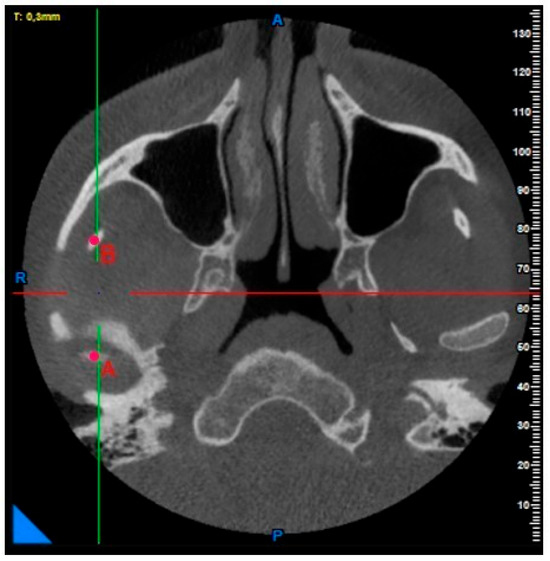

A Morphometric Evaluation of the Mandibular Condyle, Coronoid Process, and Gonial Angle: Age and Gender Differences in CBCT Imaging

2. Materials and Methods